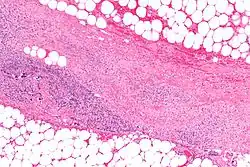

Las enzimas necrotizantes destruyen células y tejidos. Uno de los ejemplos mejor conocidos es una exoenzima producida por Streptococcus pyogenes, la cual causa Fascitis necrotizante en humanos.